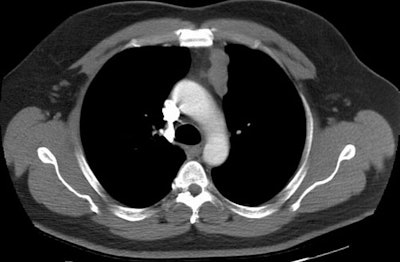

Invasive Thymoma:

The images below demonstrate an invasive thymoma. The first image demonstrates an eccentric, lobulated anterior mediastinal mas. There is ill-defined increased density within the anterior mediastinal fat, as well as the presence of a borderline enlarged mediastinal lymph node adjacent to the mass. On the lower image, the mass lacks a well defined border and again noted is infiltration of the mediastinal fat. These features suggest an invasive thymoma. (Click on images to enlarge)